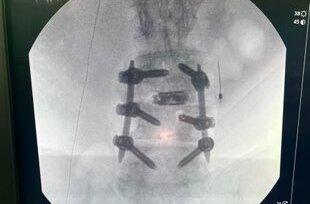

Por su parte, Luis Eduardo Camacho, amigo personal y vocero del expresidente Martinelli, también se pronunció, mediante su red social:  "Estos son los restos fragmentados del disco dañado que le fue remplazado al "brother" por la prótesis y la placa que la muestra, junto a las dos barras y los seis tornillos que le fueron colocados".